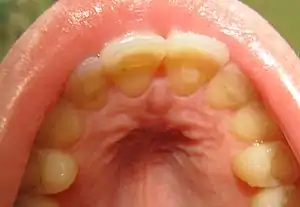

| Loss of enamel (acid erosion) from the inside of the upper front teeth as a result of bulimia | |

- Perimolysis, or severe dental erosion of tooth enamel[19]

People with bulimia are at a higher risk to have an affective disorder, such as depression or general anxiety disorder. One study found 70% had depression at some time in their lives (as opposed to 26% for adult females in the general population), rising to 88% for all affective disorders combined.[27] Another study in the Journal of Affective Disorders found that of the population of patients that were diagnosed with an eating disorder according to the DSM-V guidelines about 27% also suffered from bipolar disorder. Within this article, the majority of the patients were diagnosed with bulimia nervosa, the second most common condition reported was binge-eating disorder.[28] Some individuals with anorexia nervosa exhibit episodes of bulimic tendencies through purging (either through self-induced vomiting or laxatives) as a way to quickly remove food in their system.[29] There may be an increased risk for diabetes mellitus type 2.[30] Bulimia also has negative effects on a person's teeth due to the acid passed through the mouth from frequent vomiting causing acid erosion, mainly on the posterior dental surface.